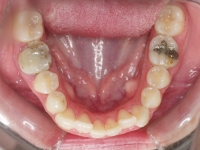

Premolar mandibular incluido + fenestración

45 incluido